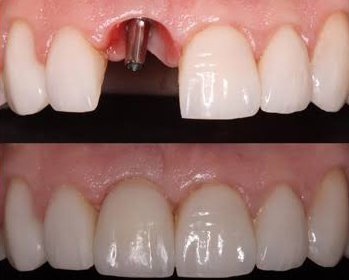

Colocação de implantes dentários para substituir dentes perdidos, garantindo mastigação adequada, estética e qualidade de vida.

Inclui pinos, coroas e próteses removíveis, devolvendo ao paciente estética e função mastigatória em casos de perdas dentárias múltiplas ou severas.